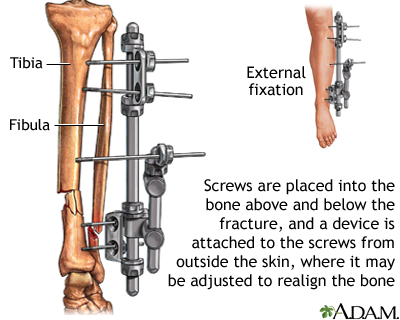

If more pressure is put on a bone than it can stand, it will split or break. A break of any size is called a fracture. If the broken bone punctures the skin, it is called an open fracture (compound fracture).

- If needed, immobilize the broken bone with a splint or sling. Possible splints include a rolled up newspaper or strips of wood. Immobilize the area both above and below the injured bone.

If circulation is poor and trained personnel are NOT quickly available, try to realign the limb into a normal resting position. This will reduce swelling, pain, and damage to the tissues from lack of blood.